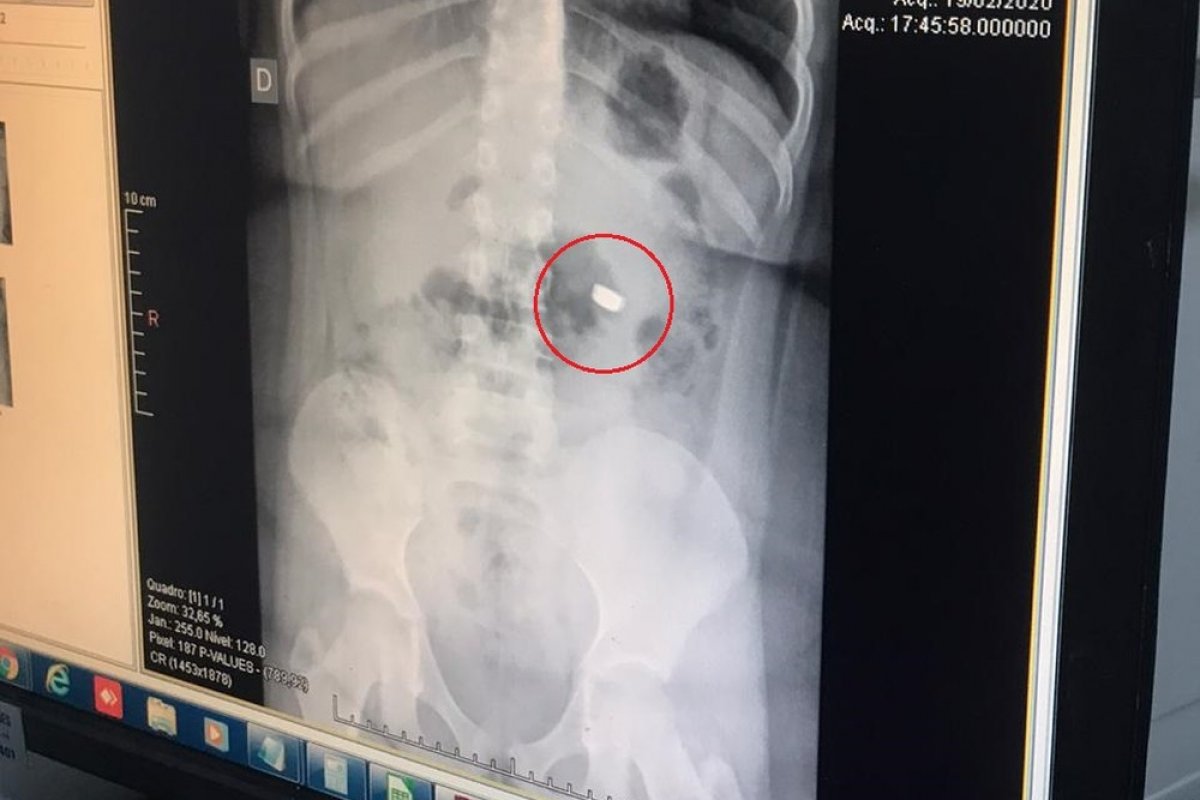

Foto: Reprodução/Arquivo pessoal

Em torno das 8h da última quinta (20), a bateria havia saído do estômago e seguido para o intestino, fazendo a equipe médica optar pelo expelimento através das fezes. A menina teve que fazer ao menos quatro exames de raio-x para que os médicos pudessem acompanhar o trajeto da bateria no sistema digestivo.